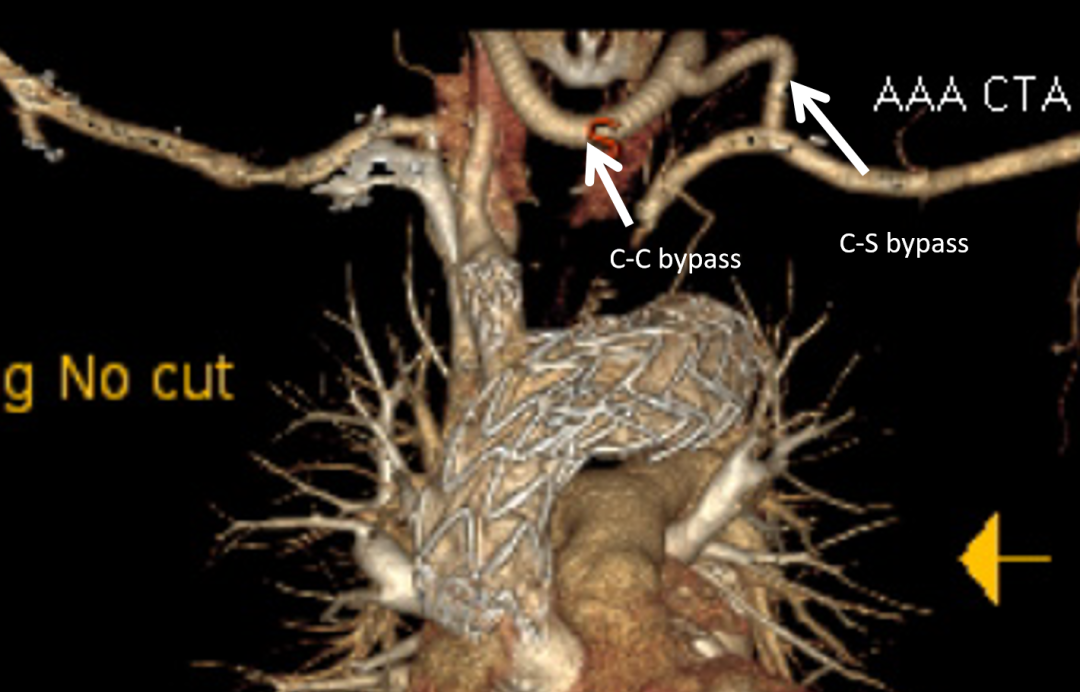

挑战Zone 0/1:突破解剖学禁区

更令人振奋的是,该器械已成功将适应症扩展至更近端的Zone 0(无名动脉)和Zone 1(左颈总动脉)。虽然这部分解剖结构更复杂,技术成功率(Technical Success)约为88.2%,但其早期结果依然令人鼓舞:

分支通畅率: 98.6%截瘫发生率: 0%

卒中风险: 约7.8%(主要与弓部操作扰动斑块有关)

图:ZONE 0/1 实验数据